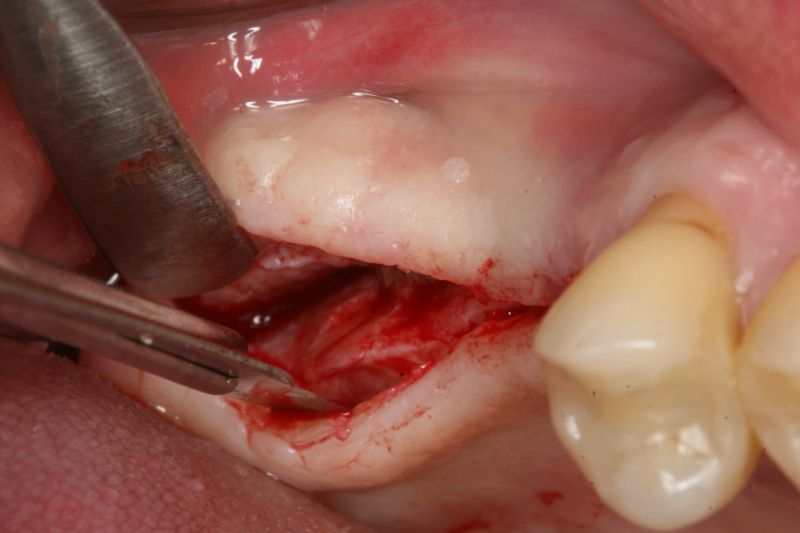

Surgical presentation of the alveolar ridge with reduced amount of horizontal bone available